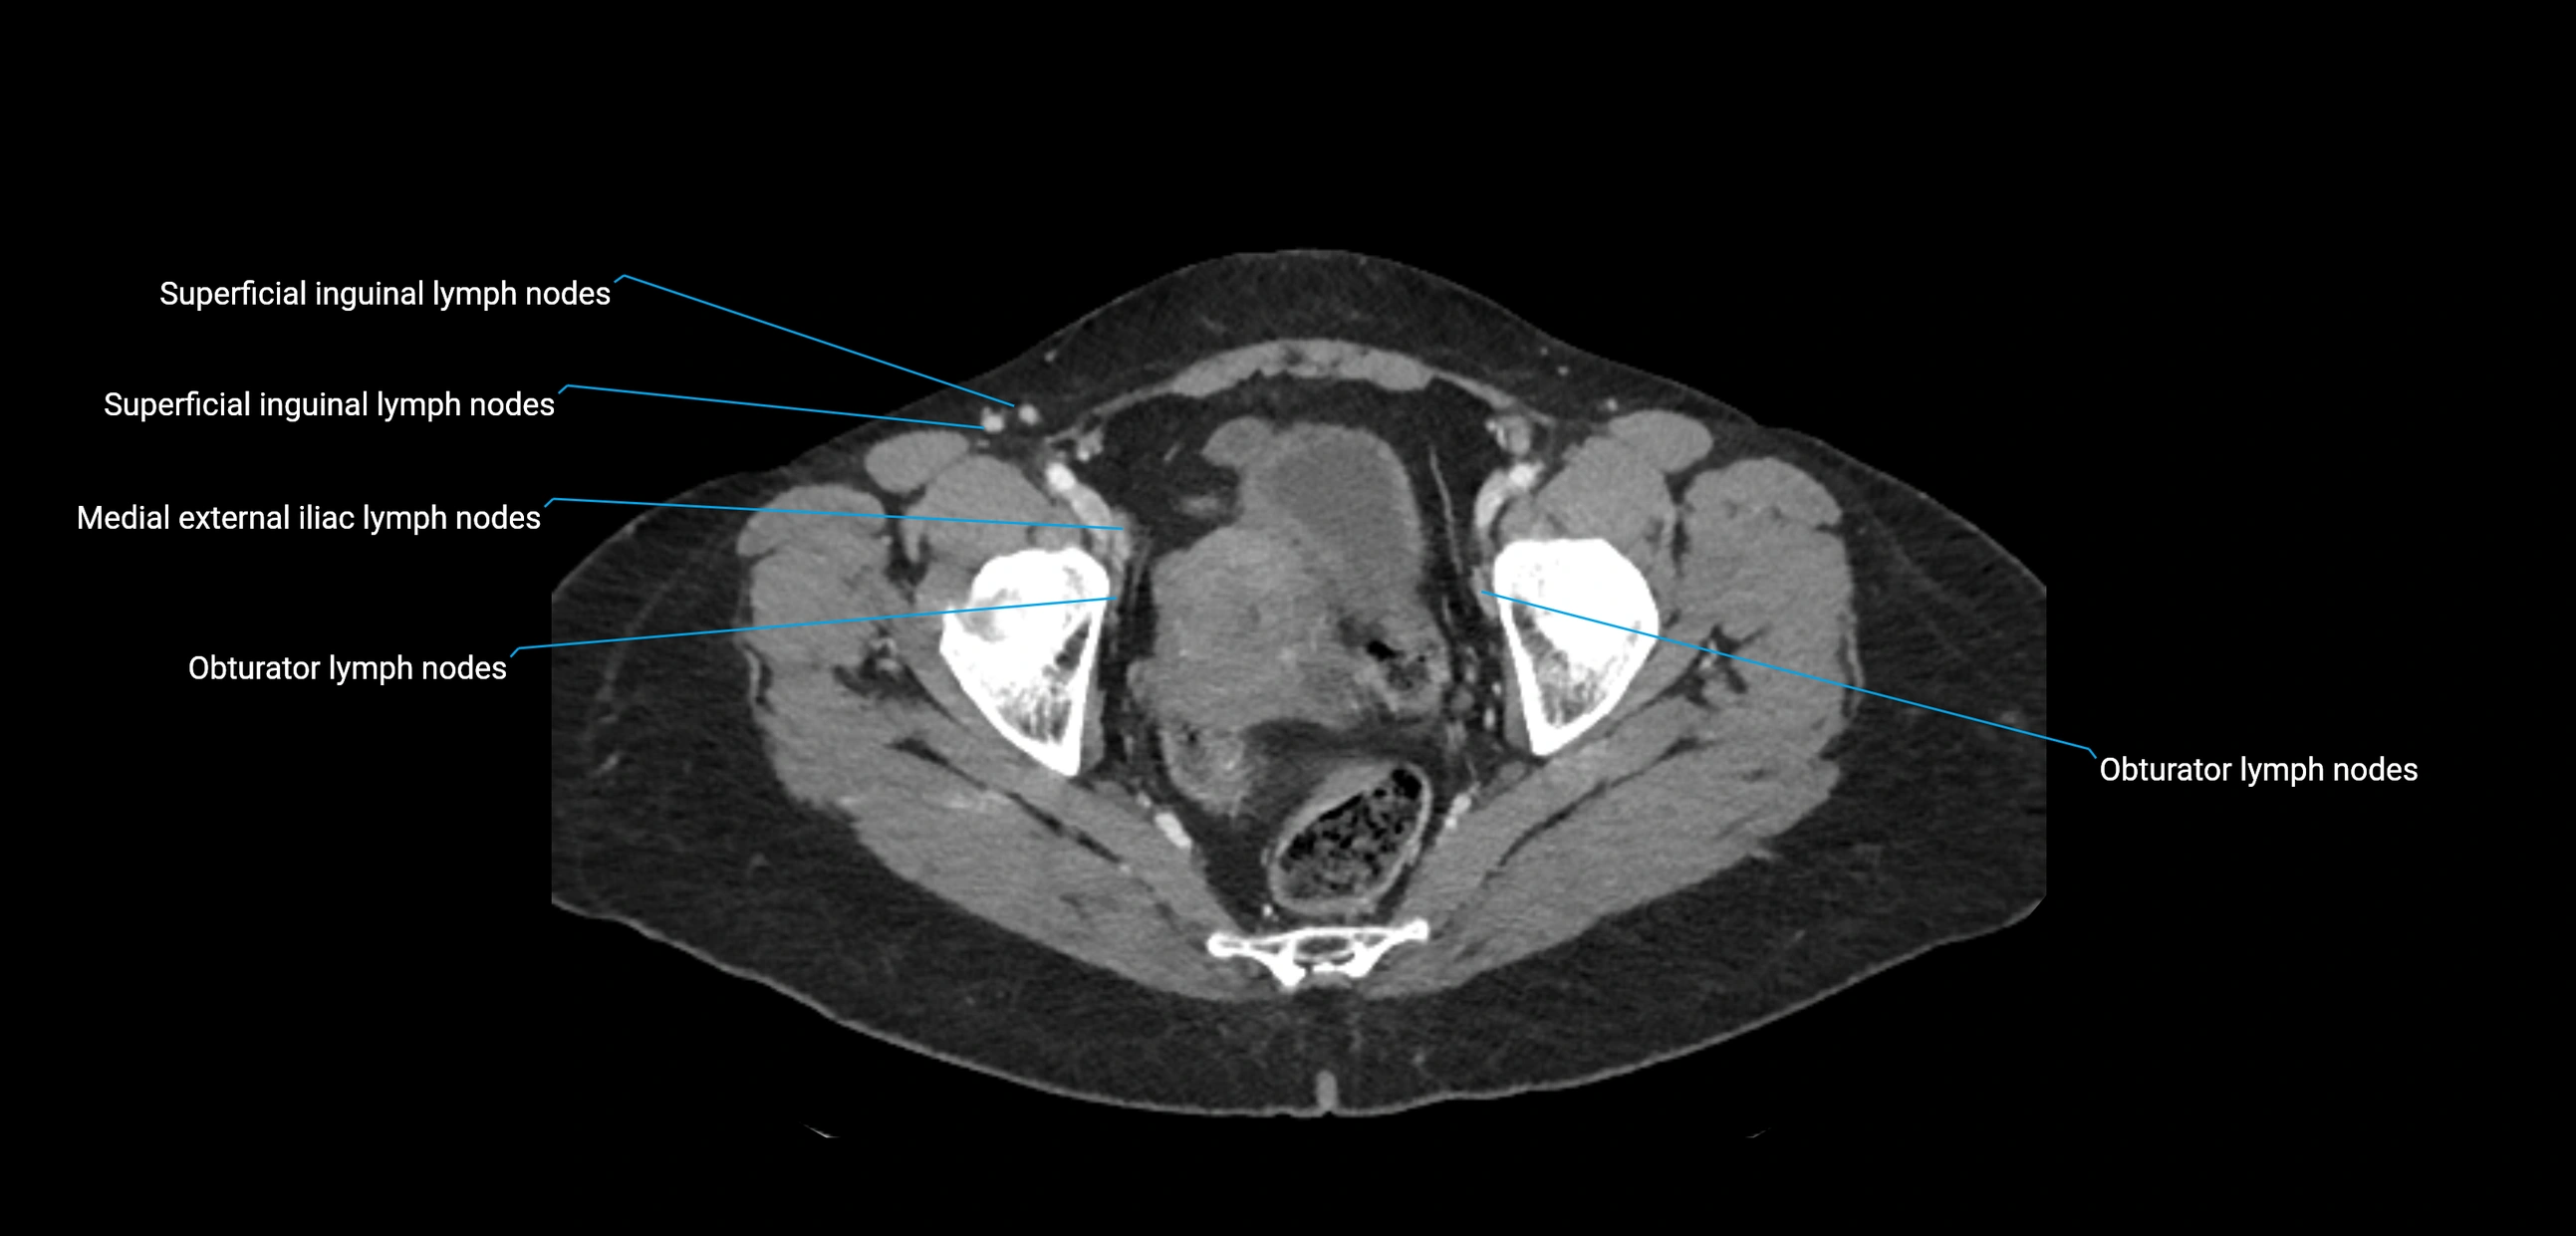

CT image

image